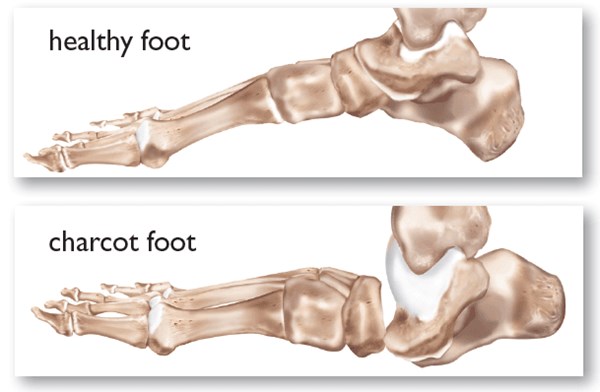

• Foot deformities caused by motor neuropathy (e.g., claw or hammer toes) or neuropathic fractures (e.g, Charcot arthropathy).[68] See section “Assessment - Physical Examination” below.

• Charcot arthropathy: In this syndrome, also known as “Charcot foot”, patients with DPN develop muscle atrophy, which leads to joint instability. Minimal or unperceived trauma results in fractures/dislocations of bones and joints. In the acute stage, there is inflammation and bone reabsorption, which weakens bones. When Charcot arthropathy becomes chronic, residual foot deformities are frequently present. The arch collapses and the foot may develop a ‘rocker bottom’ appearance. Foot deformities can lead to high pressure on areas that are not suited for weight bearing or on areas in contact with improper footwear, which will result in foot ulcers [8][68]. See “Assessment - Physical Examination - Musculoskeletal: Charcot Arthropathy”

• Charcot arthropathy: occurs in the neuropathic foot and most often affects the midfoot (tarsus and tarsometatarsal joints). In its acute phase it may present as a unilateral red, hot, swollen, flat foot with profound deformity. DFUs may or may not be present [64]. In its chronic phase, residual foot deformities are frequently present. Figure 3, Figure 4 and Figure 5.

Figure 3. Charcot arthropathy